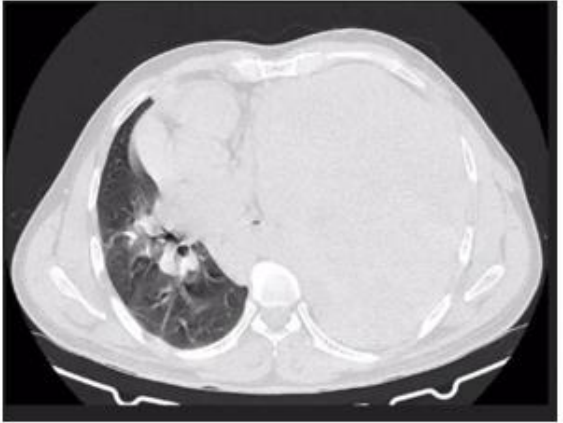

Given the radiological findings, it was considered necessary to request a contrast- enhanced chest CT scan. which reported: a vascularized solid left pulmonary mass of 24x13 cm that compromises 80% of the left hemithorax.

Image 2: Axial section of the pulmonary window with involvement of the left hemithorax by a tumor lesion.